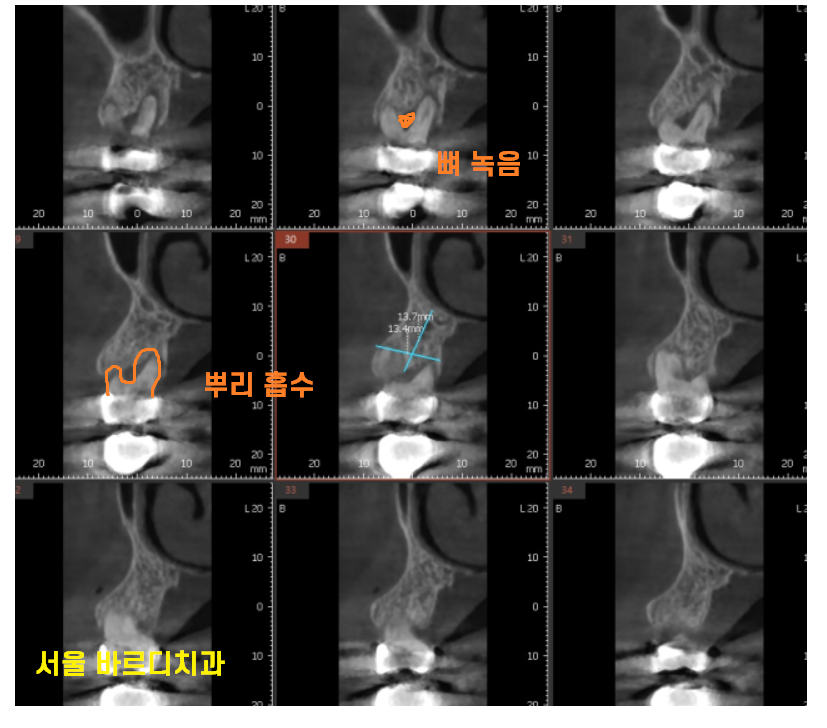

풍산동 치과에서 ct를 찍어보니

뿌리 흡수도 심하고

갈라지는 부분에 뼈도 많이 녹아있었거든요.

원래도 안좋은 치아였는데

왼쪽부터 치료하느라

오른쪽으로 주된 식사를 하셔서

보철이 빨리 빠지게 되었네요.